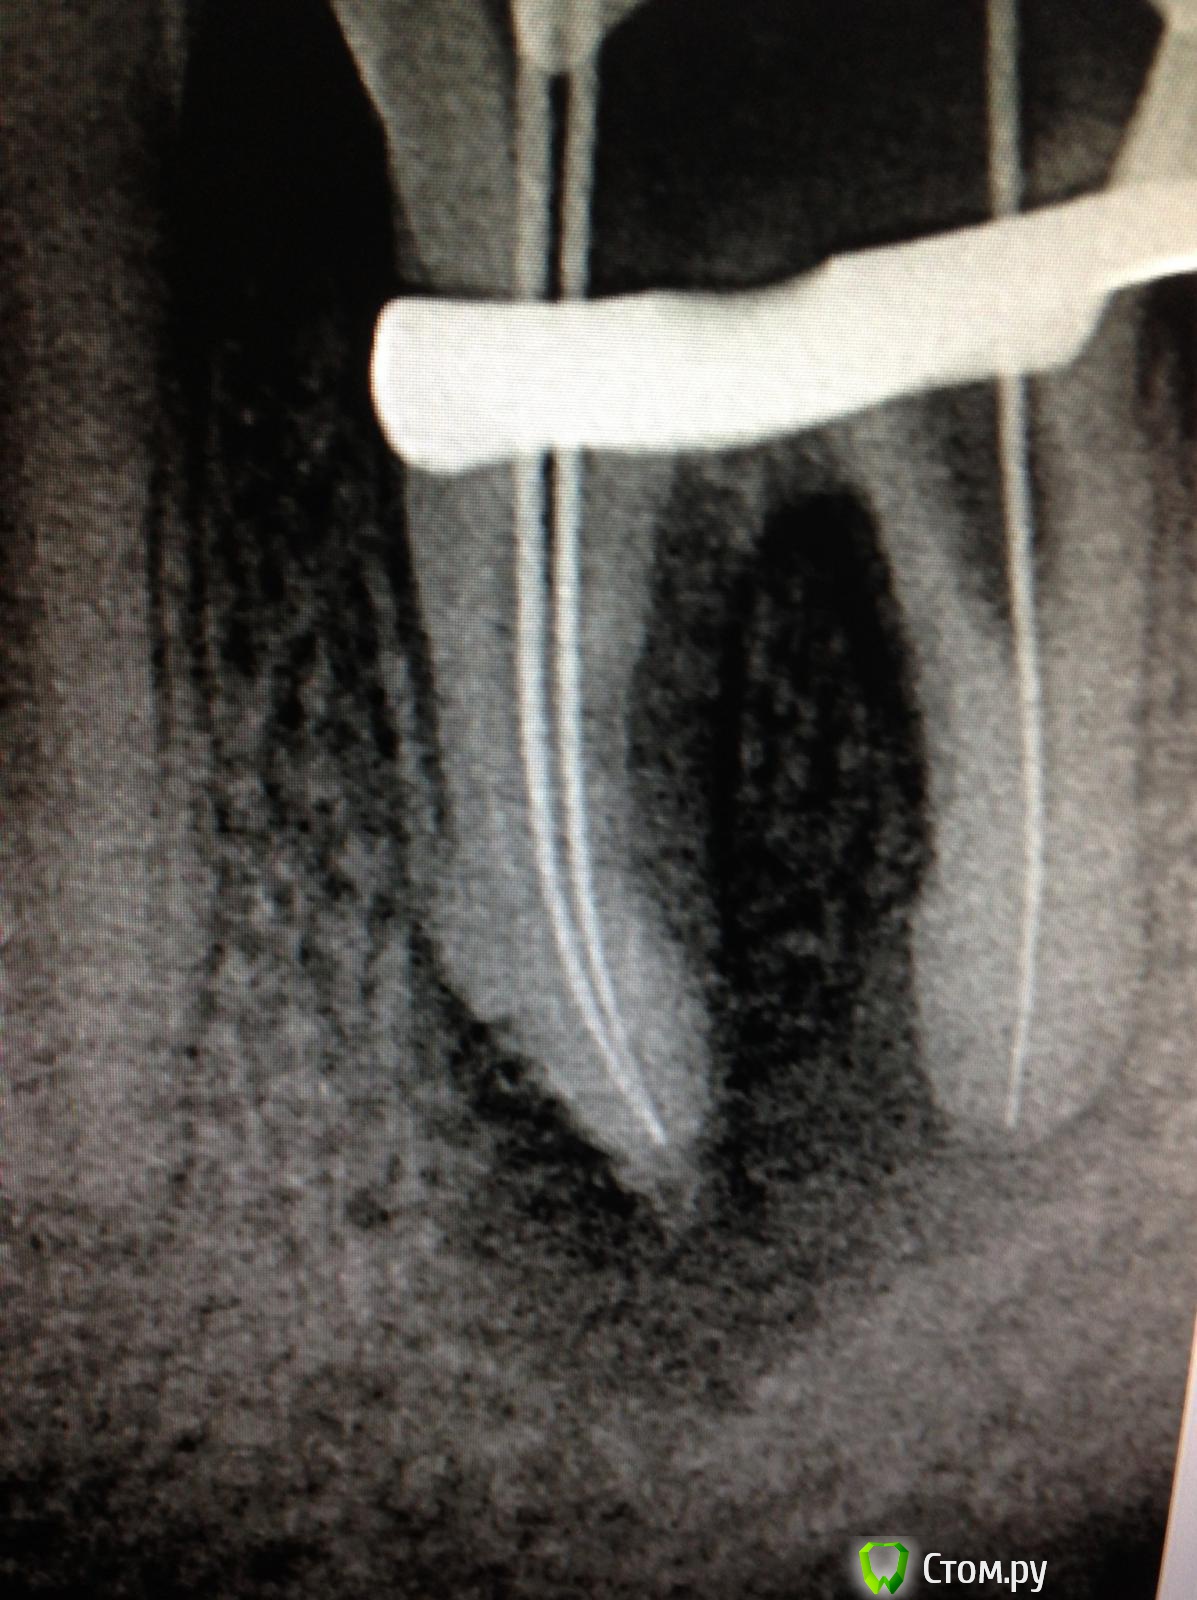

SSTi Опубликовано 9 июня, 2014 Автор Поделиться Опубликовано 9 июня, 2014 12.Жалобы на скол старой реставрации. Своих тканей 2-3 мм. Перкуссия слабо болезненна. На снимке канал запломбирован до изгиба. Первый визит- анестезия, коффер, убрал остатки пломбы и все кариозные ткани, распломбировал( была гутта), за изгибом склероз , проходила 10ка только с трудом. 10к файл, 15к файл. 15 мту, s1,s2,f1, f2, у верхушки 30.02. Гипохлор, уз, вода, эдта, хлоргексидин. Кальций. Во второй визит все отмыл и запаковал. Далее планируется вкладка и коронка. Ссылка на комментарий

faity Опубликовано 9 июня, 2014 Поделиться Опубликовано 9 июня, 2014 За апексом материал? Ссылка на комментарий

SSTi Опубликовано 9 июня, 2014 Автор Поделиться Опубликовано 9 июня, 2014 Ah+ чуть Ссылка на комментарий

faity Опубликовано 9 июня, 2014 Поделиться Опубликовано 9 июня, 2014 Ah+ чутьрассосется) Ссылка на комментарий